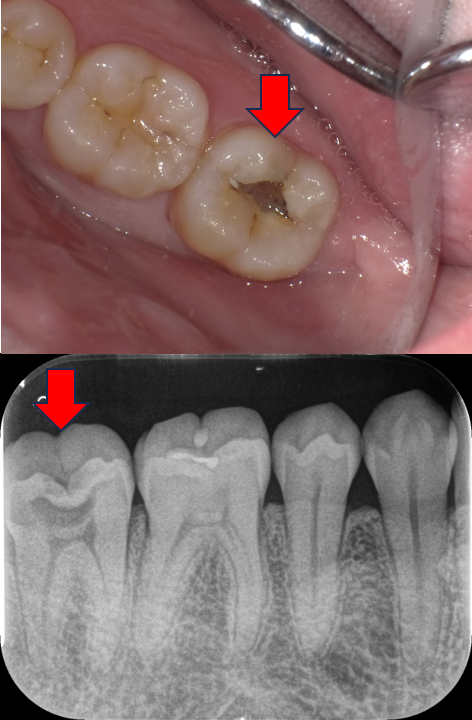

つくば市在住、「神経を残したい」深い虫歯を1回でセラミック修復治療した症例|40代男性・セレック治療

| 主訴 | 歯がしみる 神経をなるべく残したい |

|---|---|

| 診断名 | 深い虫歯(象牙質う蝕・C2) |

| 年齢・性別 | 40代 男性 |

| 治療期間・回数 | 1日 1回 |

| 治療方法 | セレックシステムによるセラミック修復 |

| 費用 | 88,000円(税込96,800円) |

| メリット | ・1日で治療が終わり、痛みも出づらい ・歯の神経に炎症が起こらず、残せる可能性が高くなる ・詰め物の接着力が高くなる |

| デメリットを・注意点 | ・保険外なので費用が高くなる。 ・歯ぎしり、くいしばりで欠けてくる可能性 |